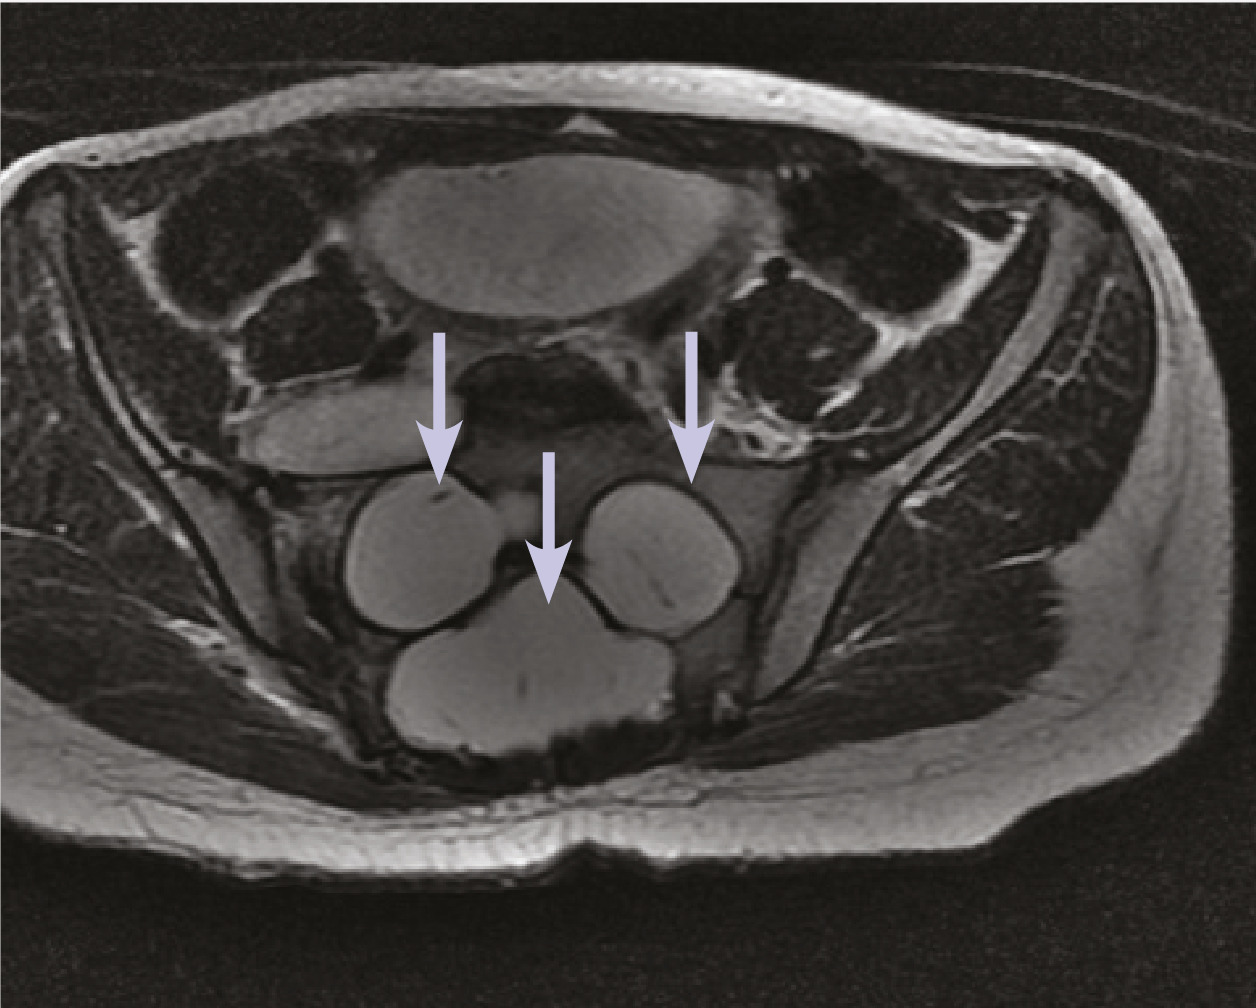

Cette jeune patiente de 12 ans atteinte d’une neurofibromatose de type 1 consultait pour des lombosciatalgies gauches. L’échographie pelvienne montrait une formation latéro-utérine droite cloisonnée. L’imagerie par résonance magnétique (IRM) pelvienne notait la présence d’une ectasie durale (fig. 1 ) responsable d’un festonnage (scalloping) [fig. 2 ] des parois des vertèbres lombosacrées, de même signal que le liquide céphalorachidien en hyposignal T1, hypersignal T2, sans rehaussement après injection de chélates de gadolinium, associée à des méningocèles élargissant les trous de conjugaison (fig. 1 ), fusant à travers les foramens intervertébraux en regard de L5 avec une extension paravertébrale antérieure. En l’absence de signe déficitaire, un traitement antalgique avec surveillance était prescrit, suivi d’une amélioration clinique.

Dans la neurofibromatose de type 1, l’ectasie durale est attribuée à une dysplasie mésodermique primitive des méninges. L’expansion des méninges sous l’effet des pulsations du liquide cérébrospinal provoque un scalloping sur la face postérieure des corps vertébraux et des hernies du sac méningé au travers des foramens intervertébraux.1 Le scalloping est observé dans la neurofibromatose dans 10 % des cas1 mais également dans le syndrome de Marfan, le syndrome d’Ehlers-Danlos et dans la spondylarthrite ankylosante. L’élargissement du canal rachidien et des foramens, la cyphose, la scoliose peuvent s’y associer.1 Les complications sont des déformations et dislocations vertébrales. Un déficit neurologique est rare.2